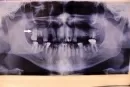

Удалять ли здоровый зуб (отмечен стрелочкой), если на верхней челюсти будет стоять съемный протез? Все остальные проблемные зубы и корни уже удалены, кроме соседнего. Мой врач-стоматолог (не ортопед) сказала, что его лучше удалить, чтобы он не мешал протезу. Хирург отказался удалять здоровый зуб и сказал, что он ничему не мешает. С ортопедом еще именно по этому зубу не консультировался.

При одном оставшемся зубе на верхней челюсти показано его удаление. Это по правилам ортопедии. Терапевт просто знает это правило, а хирург не увидел причины для удаления. Это называется "удаление по ортопедическим показаниям", и назначить его должен ортопед.

Наличие указанного зуба будет мешать полноценной фиксации протеза.